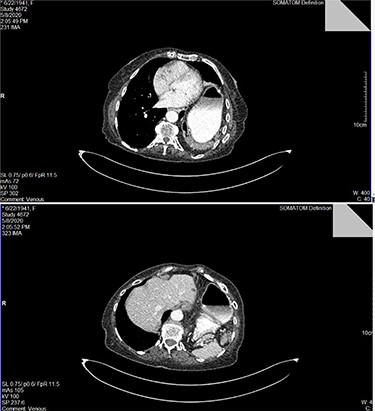

A 79-year-old female patient, referred to the outpatient surgical department, presenting with acute onset of dyspnea during minor exercise, fatigue, angina and diffuse intermittent abdominal pain. She mentioned loss of appetite and more than 15-kg weight loss during a 3-month span. Her past medical history was unremarkable. She claimed no systematic use of medication. Her vital signs and electrocardiogram (ECG) had no pathological findings. Clinical examination revealed diffuse abdominal pain during deep palpation, reduced lung sounds and presence of bowel sounds in the left hemithorax and tympanic sound during percussion ipsilaterally. Blood sampling for a full blood count and biochemistry was performed. Results appeared to be within normal range, except from a slight platelet count (PLT) elevation (583 K/μl). Chest X-ray revealed the presence of large intestine and gastric bubble within the left hemithorax. Full cardiologic workup was conducted, with no pathological findings. A contrast-enhanced computed tomography (CT) of the chest and abdomen was performed. A left hemidiaphragm elevation was revealed, with part of the stomach, transverse and left colon and spleen herniating in the left chest trough a left posterior diaphragmatic defect. All signs were compatible with a Bochdalek hernia (Fig. 1).

Top image: identification of the dilated stomach and segment of intestine in the left hemithorax in CT scan with intravenous contrast media; bottom image: identification of the spleen posteriorly to the dilated stomach within the right hemithorax.